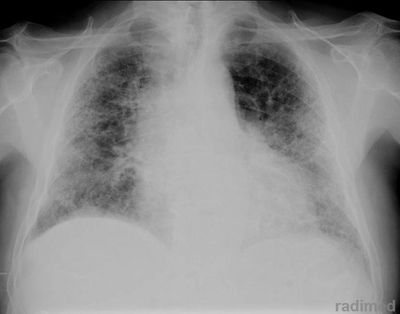

Question 27

Question

patología que se observa en la radiografía.

Answer

• enfisema

• neumonia atipica

• atelectasia

• derrame pleural